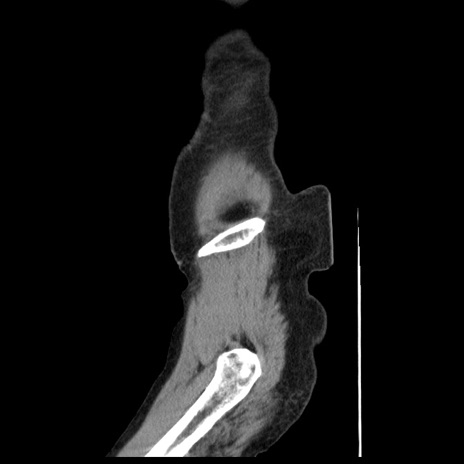

横断像